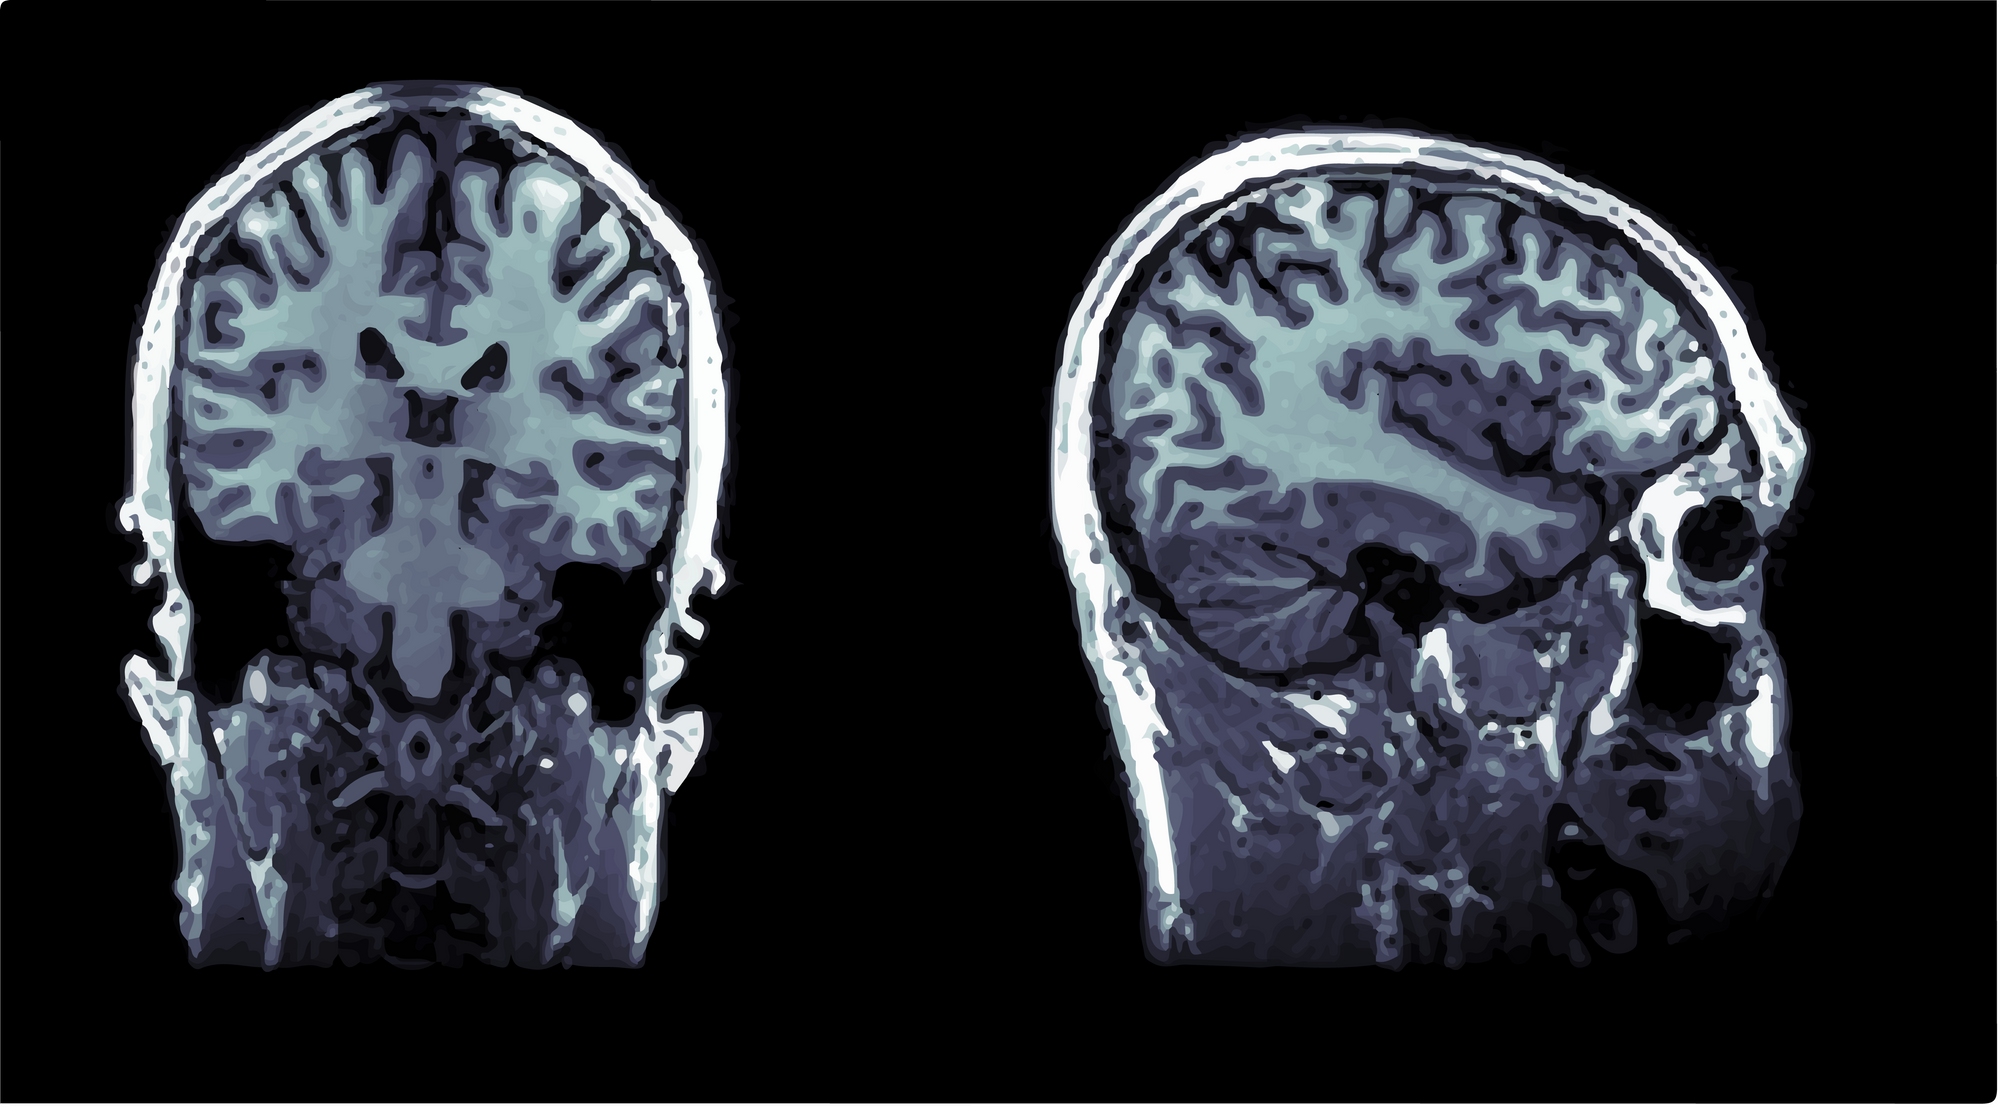

014: Brain Scans

Some visuals from a neuroscience study.

My friend sent in some images of his brain.

These are from a neuroscience research study.

They are T1-weighted structural images of his head 😳.

Beautiful and bizarre.

This was for academic research only (he's fine).